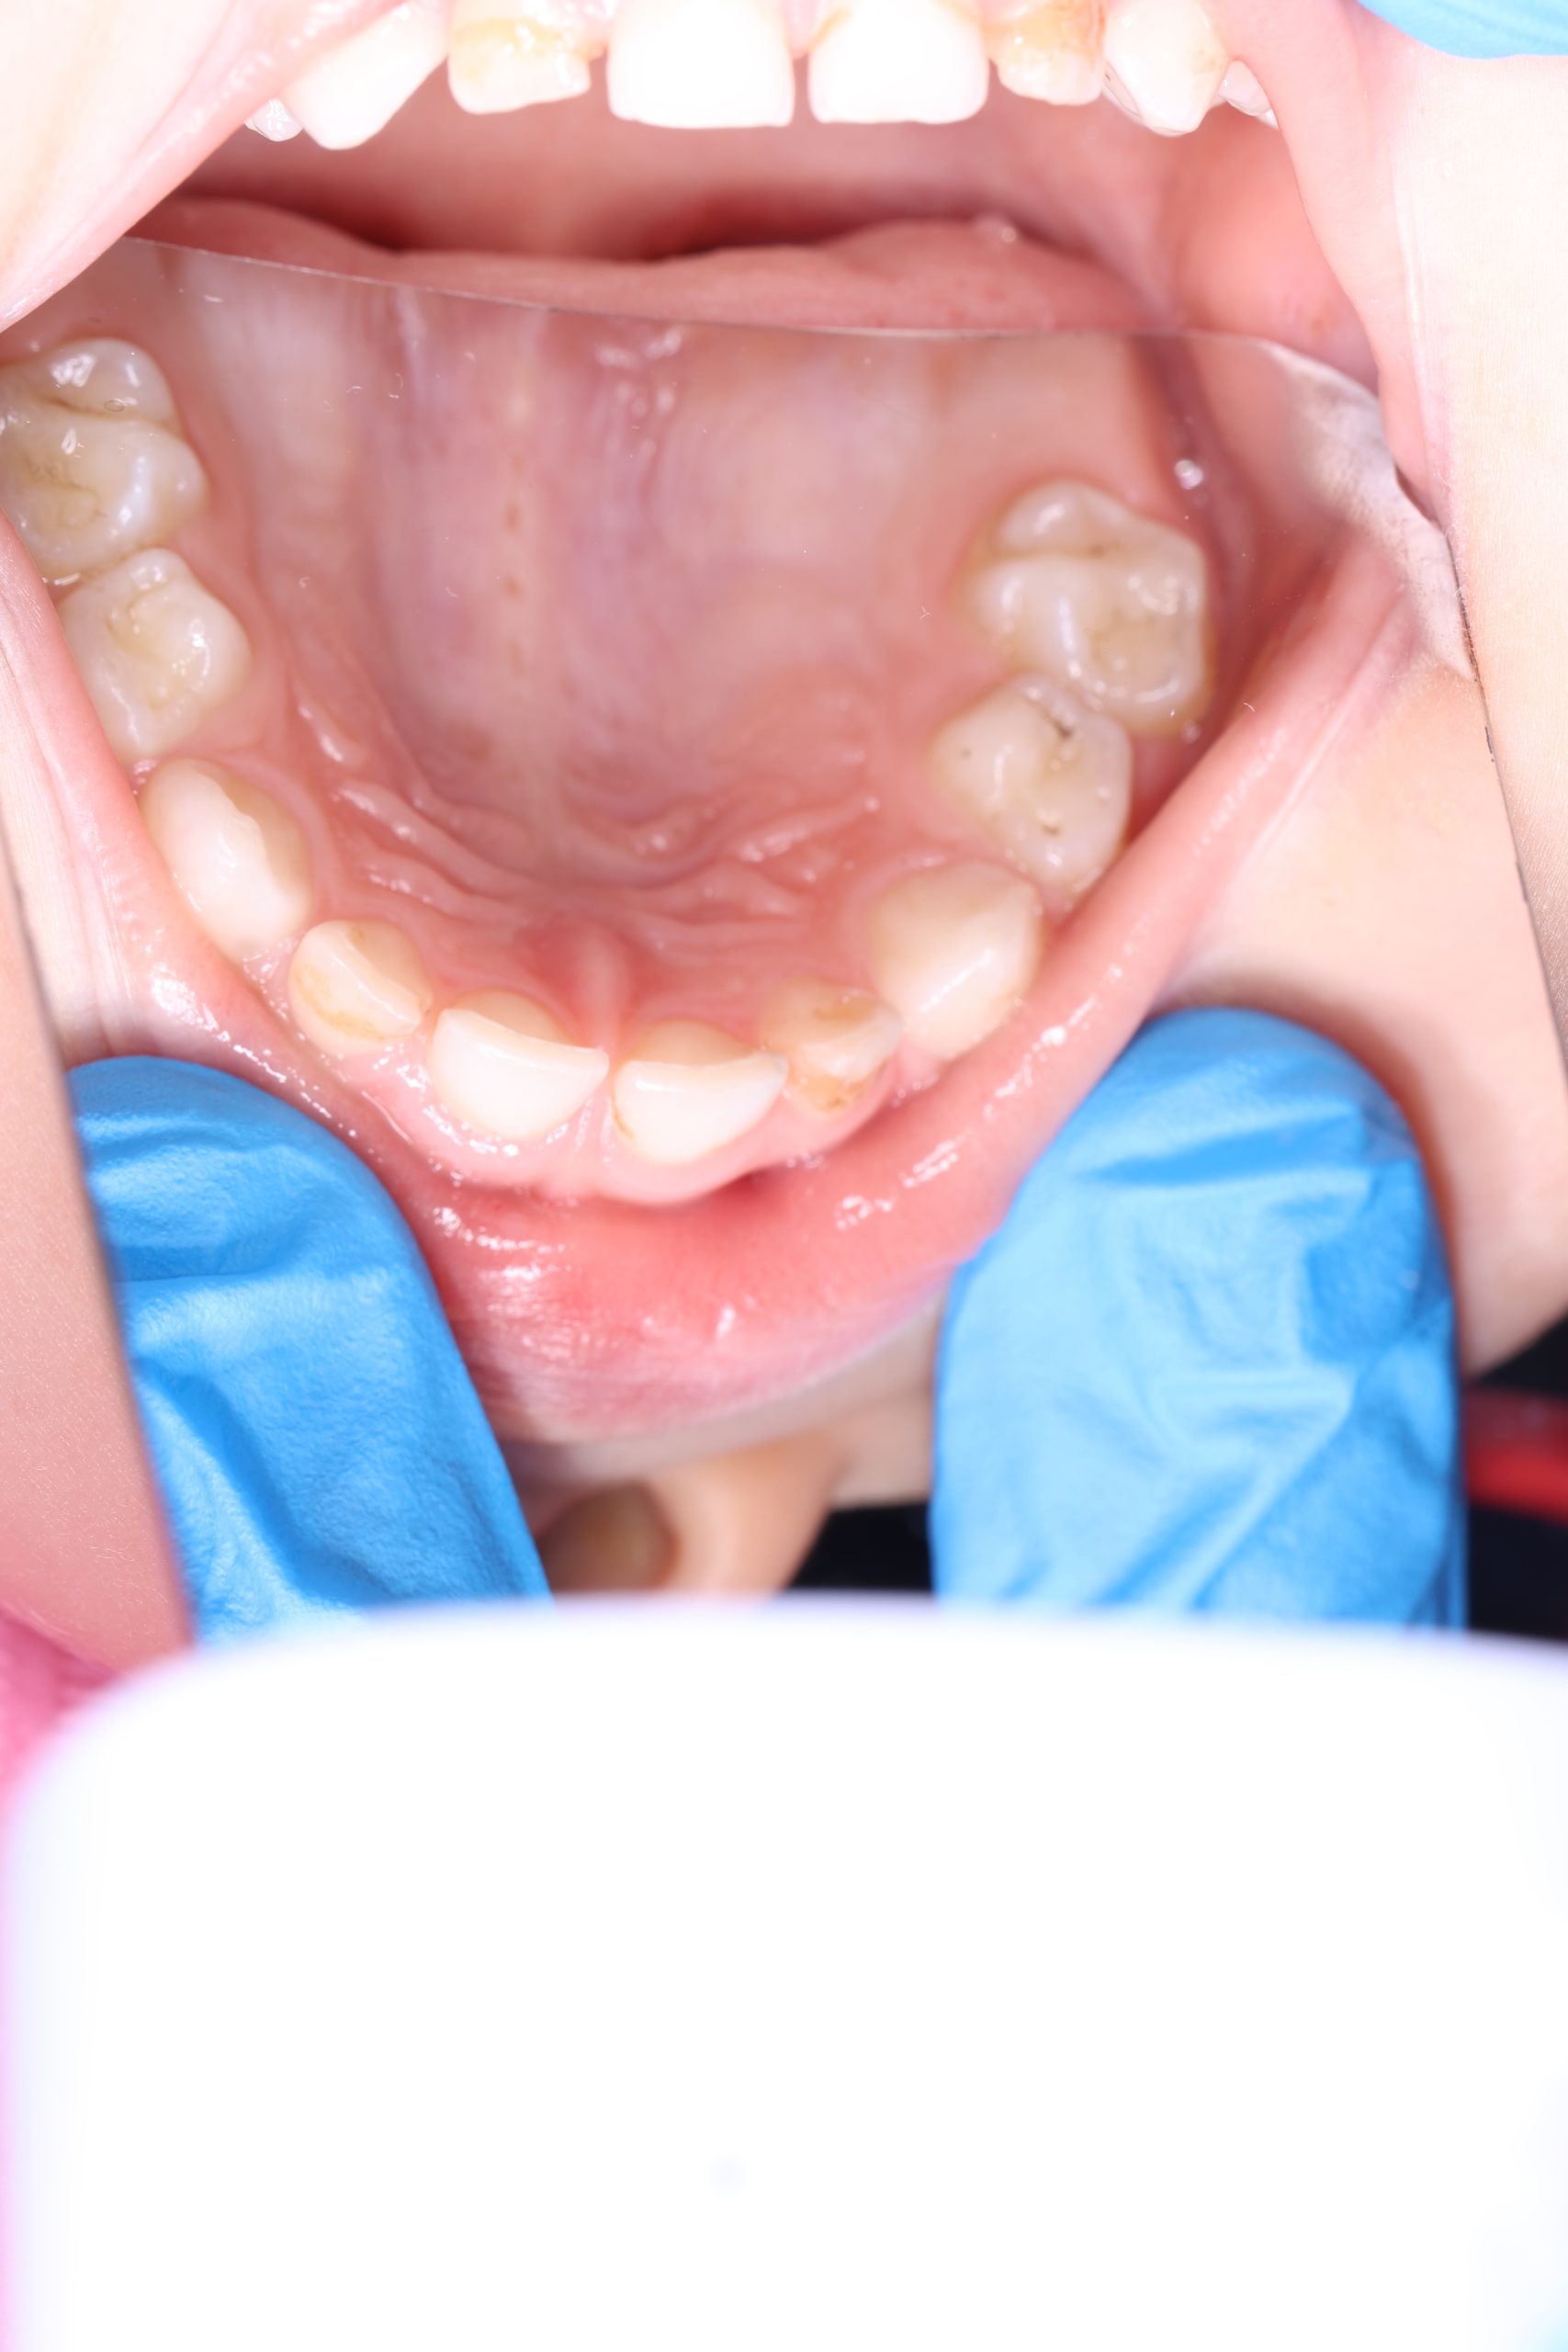

- For toddlers under 4, we provide gentle hygiene using soft rubber polishing brushes and a special tasty professional paste designed for children.

- From around age 4–5, when the child is ready, we can perform a full AirFlow cleaning using the GBT protocol.

If the child is cooperative, we perform full professional hygiene. If not, we begin with adaptive cleaning – a gentle way to introduce them to dental care and build trust.